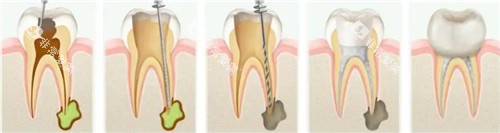

"医生,我的牙疼得强,听说要做根管治疗,在杭州大概要花多少钱?"这是杭州口腔门诊更常见的问询问题之一。根管治疗作为治疗牙髓炎、根尖周炎的核心手段,其费用因牙齿位置、根管数量、技术难度和医院等级差异显著。

2025年杭州口腔市场呈现明显的技术分层:

传统根管治疗:依赖手感与经验,成功几率约75%

显微根管治疗:借助手术显微镜(放大20-30倍),成功几率提升至92%